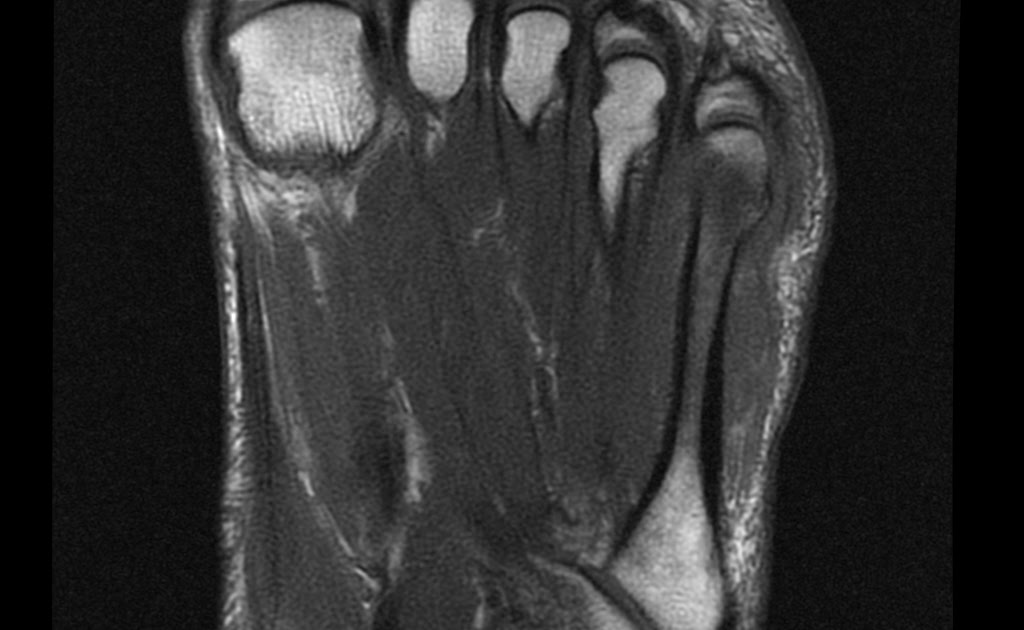

Foot Gout Mri . while mri is not a new imaging technique, recent investigations into mri in gout have altered our understanding of the disease. mri of gout magnetic resonance (mr) findings in gout include erosions, reactive bone marrow. mri is helpful in the localization of gout deposit and can show gout in the deeper tissues like the spine. gout is an inflammatory arthritis and any joint can be involved in gout, but the first mtp joint is the most common.

while mri is not a new imaging technique, recent investigations into mri in gout have altered our understanding of the disease. gout is an inflammatory arthritis and any joint can be involved in gout, but the first mtp joint is the most common. mri of gout magnetic resonance (mr) findings in gout include erosions, reactive bone marrow. mri is helpful in the localization of gout deposit and can show gout in the deeper tissues like the spine.

Foot Gout Mri mri is helpful in the localization of gout deposit and can show gout in the deeper tissues like the spine. while mri is not a new imaging technique, recent investigations into mri in gout have altered our understanding of the disease. mri of gout magnetic resonance (mr) findings in gout include erosions, reactive bone marrow. mri is helpful in the localization of gout deposit and can show gout in the deeper tissues like the spine. gout is an inflammatory arthritis and any joint can be involved in gout, but the first mtp joint is the most common.

From www.medicalimages.com

STOCK IMAGE, mri of gout of the foot with tophaceous deposits tophi in Foot Gout Mri gout is an inflammatory arthritis and any joint can be involved in gout, but the first mtp joint is the most common. mri of gout magnetic resonance (mr) findings in gout include erosions, reactive bone marrow. while mri is not a new imaging technique, recent investigations into mri in gout have altered our understanding of the disease.. Foot Gout Mri.